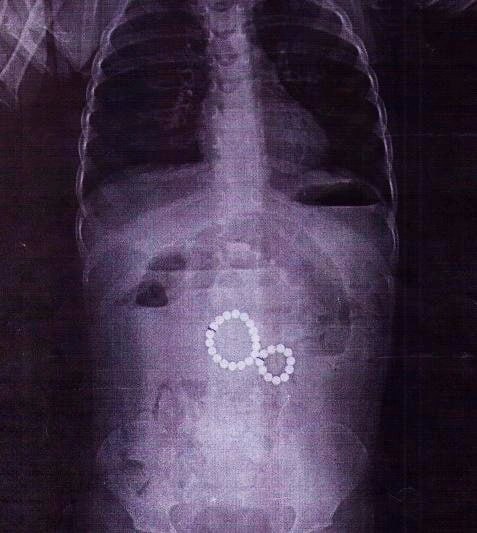

Рентген показал, что магниты соединились в «восьмёрку» и повредили кишечник, вызвав перитонит. Хирурги удалили все инородные тела и устранили осложнения. Сейчас малышка идёт на поправку.